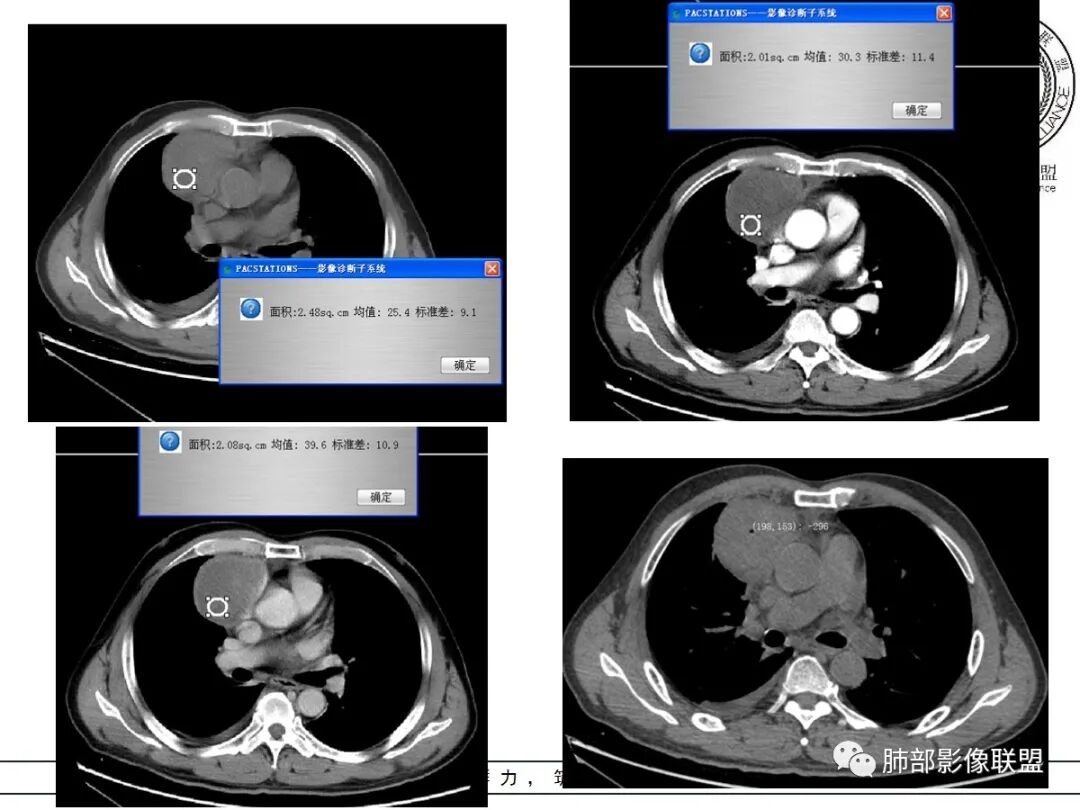

岁月:男性,68岁,右胸痛一天,无家族史,右上中叶纵膈旁占位;抽烟50年,3天1包。wbc高。与纵膈脂肪间隙不清,胸水,快进快出 分叶,有血管样强化,9.1-11.4-10.9。诊断:错构瘤,似乎都符合;但如果恶性放在前面,肉瘤、恶性。鉴别:错构瘤、侵袭性胸腺瘤;处理:经皮肺活检、手术。

周围脂肪间隙密度增高,内部小点状很低密度影

右侧少量胸水

19日,4天后, 内部低密度影有,周围渗出增多,胸水增多

薄膜状强化

脂肪密度明显,还有钙化、囊性病变,支持含脂质类病变破裂

结果:符合B型胸腺瘤伴出血,坏死囊性变,局部脓肿形成

3.右上纵隔囊实性占位,边界清楚。中央见点状脂肪密度影,边缘见一点状钙化影,增强不均匀环形强化。

4.四天内病灶变化快,块影增大且不规则,包膜似不完整,边界不清,上份可见浸润或渗出,与周围心脏大血管及心包等间隙不清。胸水增多。

第一次的检查符合胸腺瘤影像学改变,短期内的形态学改变及突然出现的边界模糊或浸润等,符合出血或炎症。